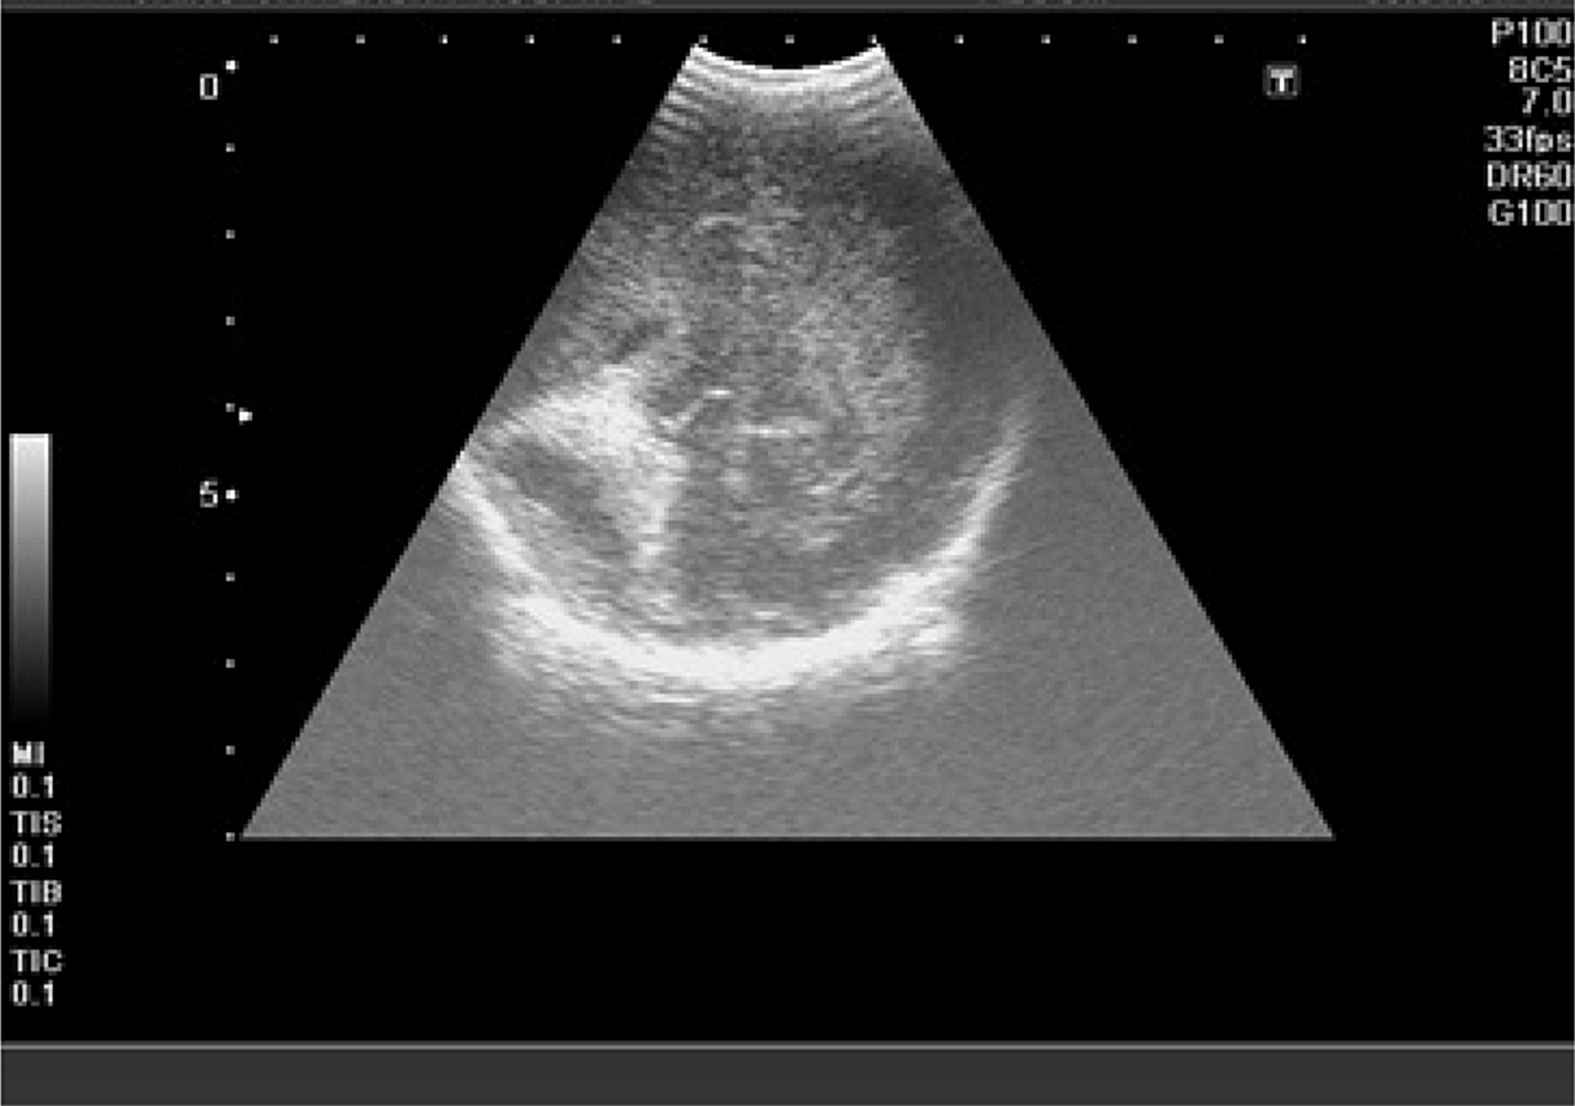

Intraventricular hemorrhage 4th grade in case 1.

Intraventricular hemorrhage 3rd grade in case 2.